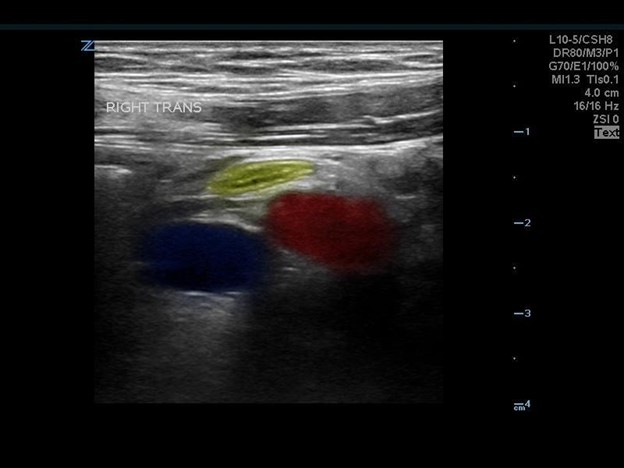

Color flow can help delineate the iliac artery and vein from bowel and musculature and should be utilized during the appendix ultrasound. An emphasis should be made to continue using graded compression, as consistent pressure can fully compress a normal appendix making it more difficult to locate. You should save clips and still images with and without compression in multiple planes and apply color flow over the appendix as well.

The appendix is most reliably found in the right lower quadrant; the base extends from the proximal cecum and lies anterior to the psoas muscle and the right iliac vessels. Most of the time the distal tip is retrocecal, though the challenge in localization is augmented as the appendix can be pelvically oriented (Images 5 and 6) or directed elsewhere in the abdomen. The normal appendix is tubular, non-peristalsing, compressible, and blind-ended, measuring less than 6 mm. (Image 7)

Image 5. Normal appendix

Image 6. Normal appendix (Yellow: Appendix, Red: Iliac Artery, Blue: Iliac Vein)